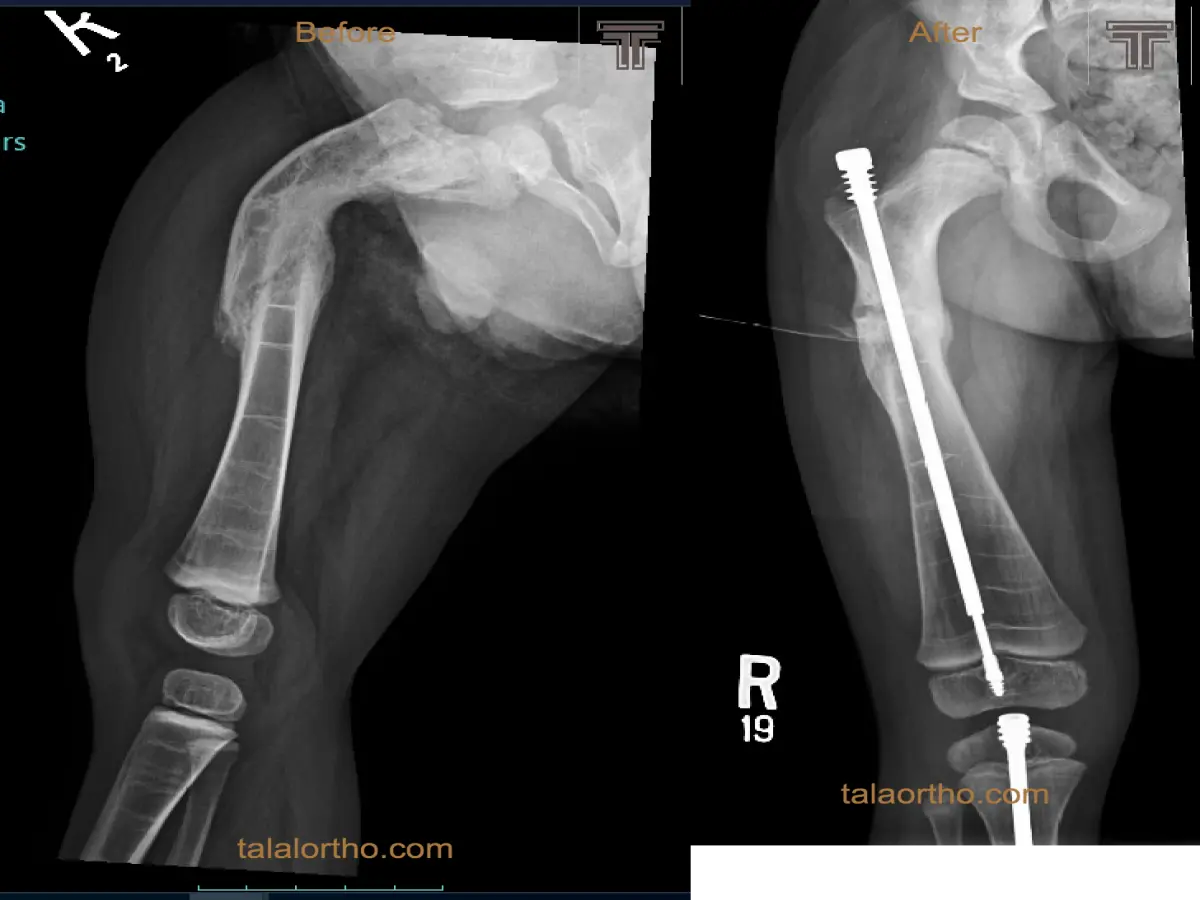

العظم الزجاجي هو مرض وراثي يؤدي الى كسور متعددة وتشوهات/تقوسات في العظام. تعالج الكسور في أول سنتين بالعادة بالجبس ...

بخلاف الكسور العادية في الاطفال فإن مثل هذا الكسر يحدث دون اصابه والتآمه صعب. في حال التآمه بعد التدخل الجراحي ...